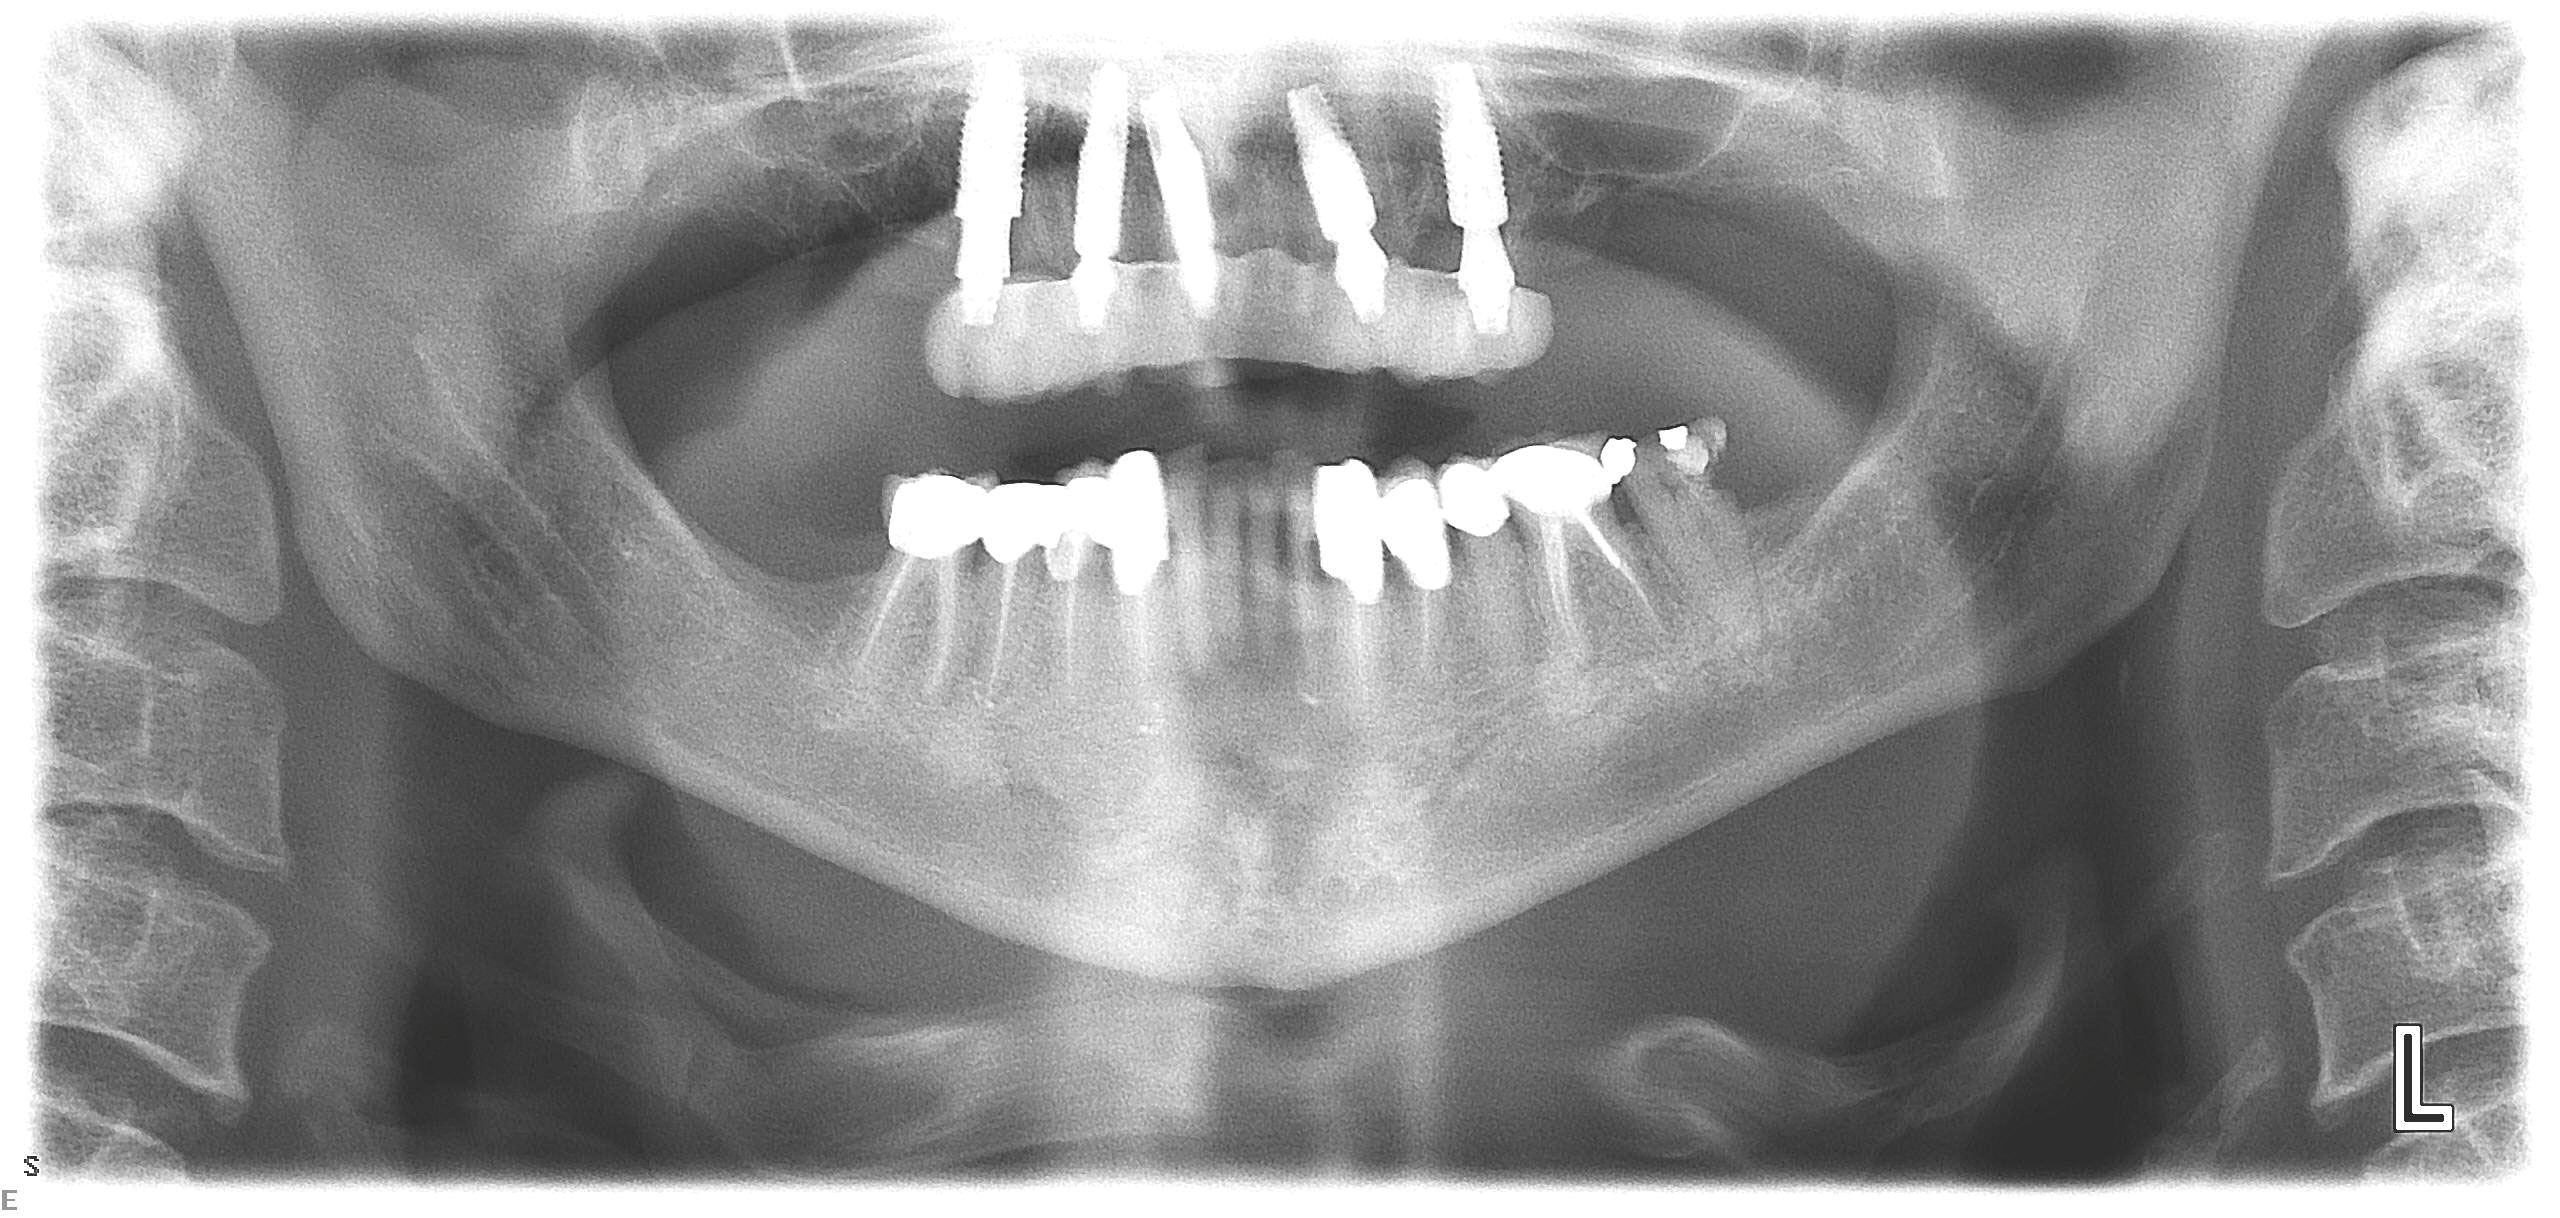

Fig 21. Postoperative panoramic radiograph on the day of surgery.

Figure 21

Fig 22. Postoperative periapical x-rays on the day of surgery demonstrating the provisional restoration with ti-bases fully seated to multi-unit abutments and ideal immediate implant placement.

Figure 22